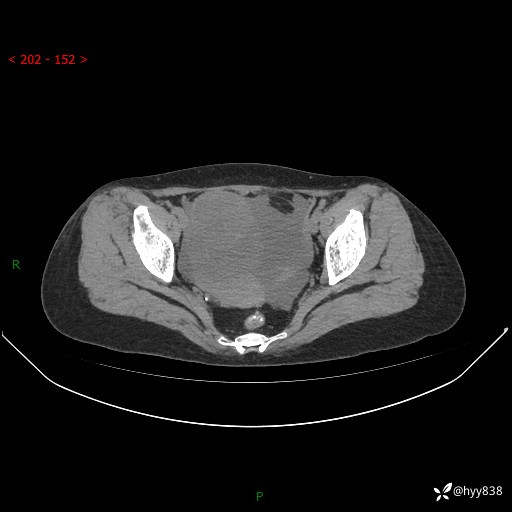

老年女性,尿频2月。超声发现盆腔囊实性占位,CT能否明确诊断---结果公布

现病史:患者绝经3-4年,期间无阴道出血及排液。患者近2月感尿频,自行口服中药治疗,症状无明显缓解。2024-4-25日于我院门诊就诊,行阴道彩超示:子宫肌瘤(大小约12*10mm,后壁),子宫右前方囊实性占位性病变(大小约126*82mm肿块声像,边界尚清,以无回声为主,可见范围约84*27mm稍高回声),内膜3mm。建议手术治疗。门诊以“卵巢囊肿”收入院。 病程中精神、食欲、睡眠可,大小便正常,体重体力无明显变化。

腹盆CT平扫